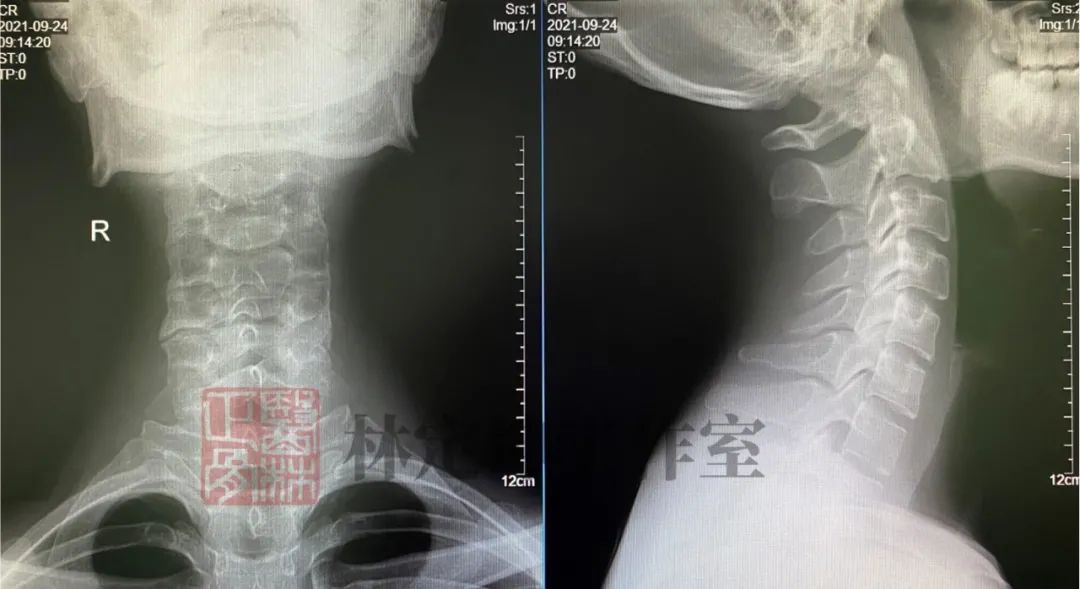

02 X光片检查

在颈椎病的检查中,X光片检查是最为常见的一种方法。这项检查相当于是 利用X射线给我们的颈部拍了一张平面影像照片 。X射线会因被照射物的密度不均匀而在底片上形成黑白不同的颜色,从而能够反映出我们颈部的 骨性结构 。

可得信息:

(1)判断颈椎的大体形态、曲度、稳定性;

(2)判断骨头结构是否出现破坏的情况;

(3)是否出现骨质增生或先天畸形的情况。